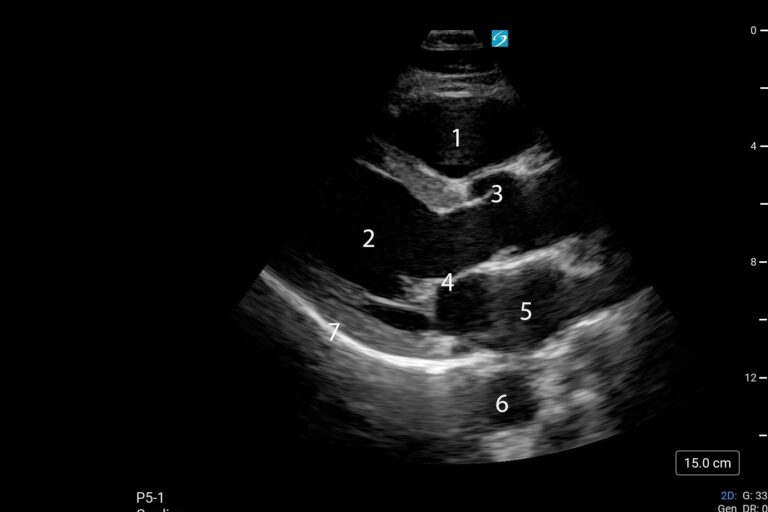

POCUS NEL CONTESTO PREOPERATORIO – CUORE Fabio Magarotto1, Federica Arturi1, Gabriele Melegari2 Università degli Studi di Modena e Reggio Emilia, Scuola di Specializzazione Anestesia e Rianimazione, Terapia Intensiva e del…